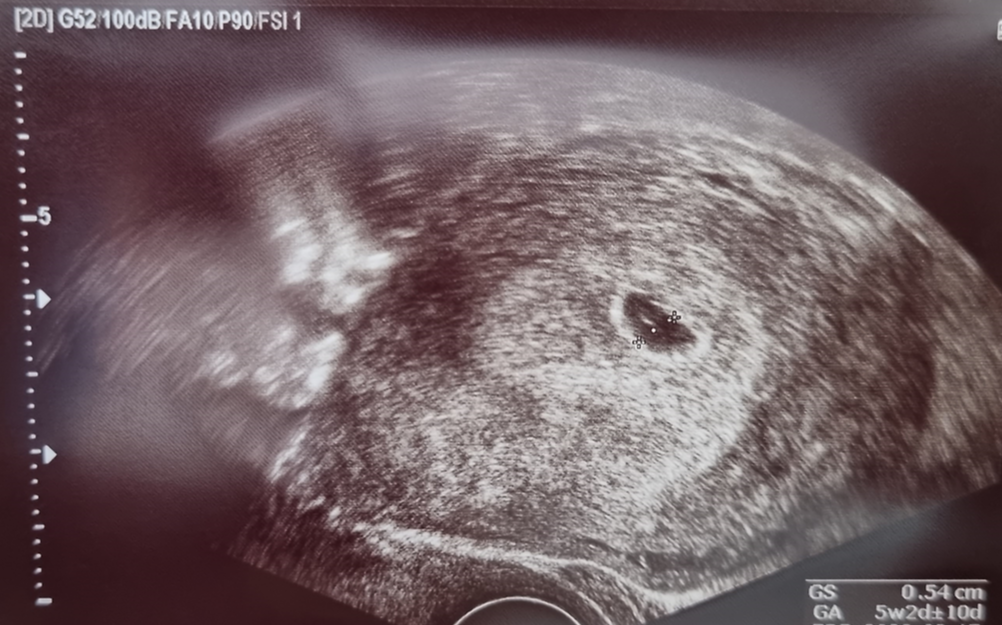

D-237 임신 5주 차. 티끌이를 처음 본 날.

아내가 임신테스트기를 확인하고 초음파를 처음 보러 산부인과를 갔다. 가슴이 너무 뭉클해진다. 내가 아이를 가졌다니. 우리 부부를 닮은 아이가 세상에 나올 생각 하니 가슴이 뜨겁다. 초음파사진을 받아봤는데 아직 콩알같이 자그마하다. 태명은 티끌이로 정했다. “네 자손이 땅의 티끌 같이 되어서 동서 남북에 편만할찌며 땅의 모든 족속이 너와 네 자손을 인하여 복을 얻으리라” 올해 신년사 말씀을 새기면서 하나님이 아이를 주실 것으로 믿었고, 아이를 가지면 태명은 무조건 티끌이로 해야겠다 생각했었다. 아내는 무슨 아기가 티끌이냐고 하찮다고 생각하는 듯하다. 나는 태명은 된 발음이나 거센 발음이 있어야 아이 반응이 더 좋으며, 낮은 사람이 더 크게 된다고 설득하니 아내는 마지못해 받아들인다.